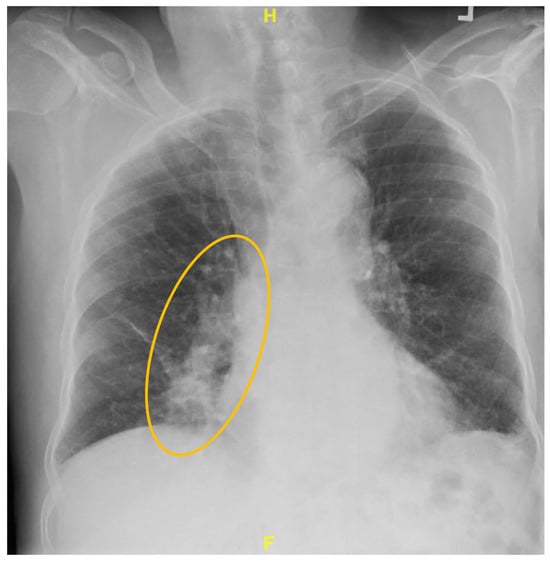

Not All PET-Avid Endobronchial Lesions Are Malignant: A Case of Chronic Foreign Body Aspiration

Background: Low-dose CT scanning is a key tool in lung cancer screening, enabling the detection of clinically significant abnormalities in asymptomatic individuals and often prompting further diagnostic evaluation. Case Presentation: We describe the case of an 80-year-old man with a heavy smoking history [...] Read more.

Background: Low-dose CT scanning is a key tool in lung cancer screening, enabling the detection of clinically significant abnormalities in asymptomatic individuals and often prompting further diagnostic evaluation. Case Presentation: We describe the case of an 80-year-old man with a heavy smoking history who was found to have a new right middle lobe collapse on screening CT. Subsequent positron emission tomography-computed tomography (PET/CT) imaging demonstrated mild fluorodeoxyglucose (FDG) uptake (SUVmax 2.7), raising concern for a low-grade endobronchial malignancy versus mucoid impaction. Flexible fiberoptic bronchoscopy revealed a large exophytic endobronchial mass occluding the airway. Histopathologic examination of the biopsy sample unexpectedly revealed vegetable material, consistent with chronic foreign-body aspiration. Discussion: Unrecognized aspiration events are relatively common in elderly adults and can mimic malignancy on imaging. This case highlights an important diagnostic pitfall: inflammatory endobronchial processes, including foreign-body granulomas, can demonstrate FDG uptake and mimic malignancy. Conclusion: Clinicians should maintain a broad differential diagnosis when evaluating PET-avid endobronchial lesions, especially in elderly patients. Full article

Show Figures

Figure 1